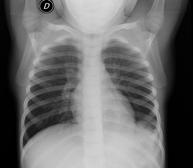

Tècnica que usa els raigs X a través de la qual s'obtenen imatges dels sins paranasals per al seu estudi. Indicacions: cefalea, tos crònica. - RX Tòrax

Una radiografia de tòrax és una tècnica mitjançant la qual, amb l'ús d'una petita dosi de radiació, s'obté una imatge bidimensional de la caixa toràcica i el seu contingut (pulmons, cor, mediastí, etc. ). És una de les proves mèdiques realitzades més comuna. - RX Abdomen